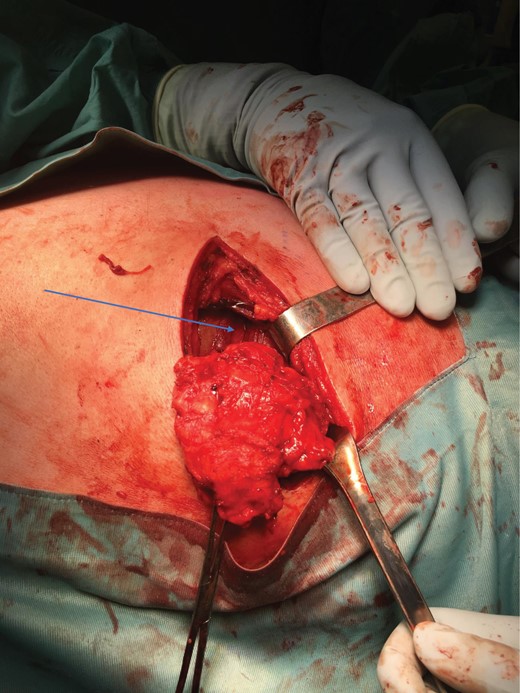

Surgery was uneventful but the tumour was quite deep below the lattisimus dorsi and serratus anterior muscles, and lying on the posterior rib cage (Figs 5–7).

Tumour exposure(forceps) below the lattisimus dorsi (blue arrow).